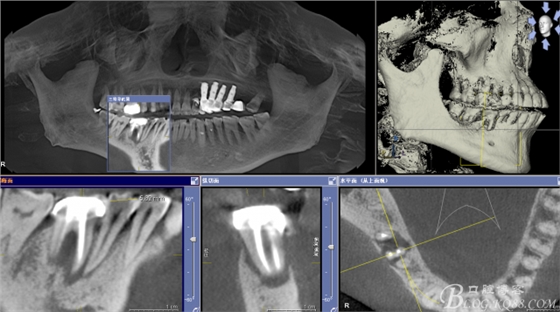

CT可見(jiàn)根管內(nèi)有白色顯影物和根周較大暗影

從根管影像看治療還是不錯(cuò)的,

懷疑牙根微裂,

所以建議患者手術(shù)探查